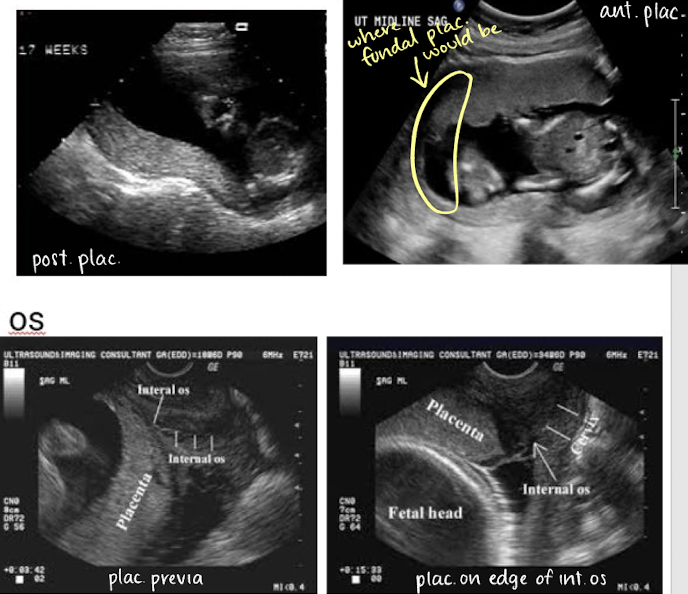

describing placental location in uterus and in relation to cervical os

in uterus

anterior

posterior

fundal (in uterine fundus)

in relationship to cervical os

close to os

away from os

covering os

if covering internal os, that is called previa